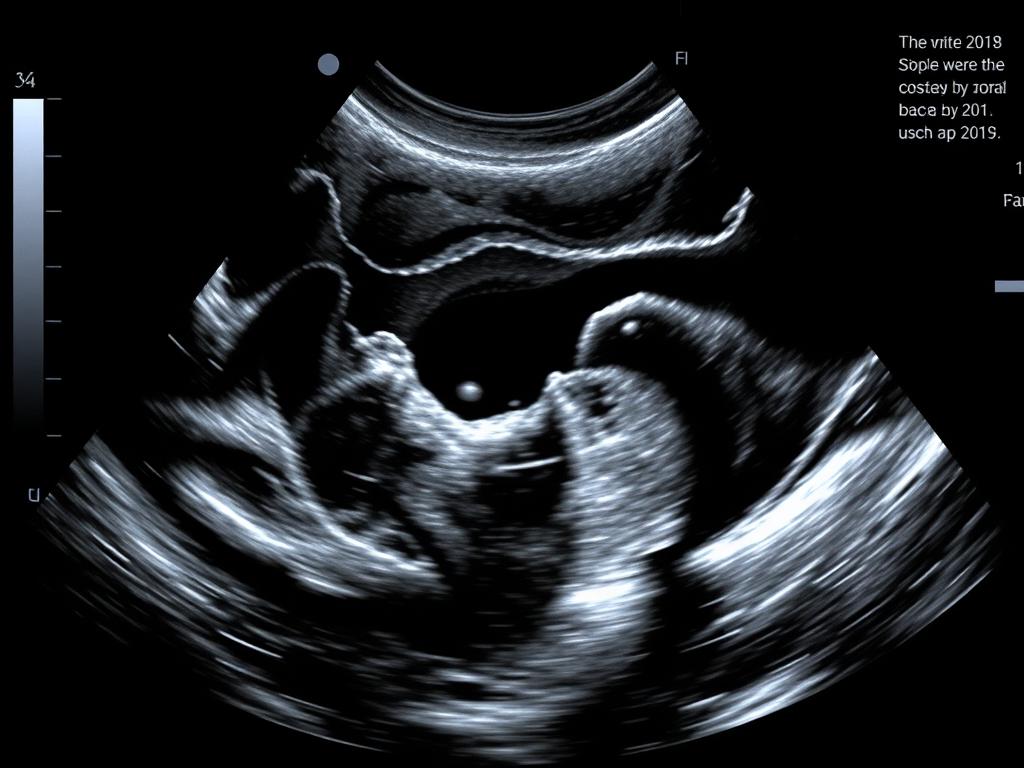

На теле иногда появляются непонятные уплотнения, шишки или припухлости. Кто-то сразу бежит к врачу, а кто-то месяцами ждёт, пока «само пройдёт». Если вас что-то беспокоит, но непонятно, что именно — УЗИ мягких тканей поможет разобраться без разрезов и боли.

Мягкие ткани — это всё, что находится под кожей: мышцы, жировая клетчатка, связки, лимфоузлы. УЗИ покажет:

Это как фонарик, который светит под кожу — врач увидит то, что не разглядеть глазом.